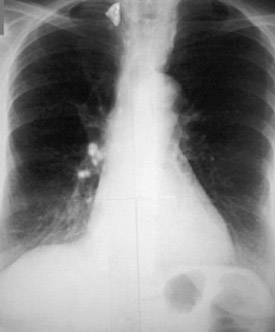

Хаммена-рича синдром (фиброзирующий альвеолит) на рентгенеСиндром Хаммена-Рича - заболевание редкое, но в последние годы встречается все чаще.

Причины болезни полностью не ясны, скорее всего, ее возникновение связано с нарушениями в иммунной системе, генетической предрасположенностью. В ткани легких, в легочных альвеолах накапливается слизь, содержащая много коллагеновых волокон, что приводит к уплотнению легочной ткани, зарастанию альвеол и препятствует нормальной работе дыхательной системы.